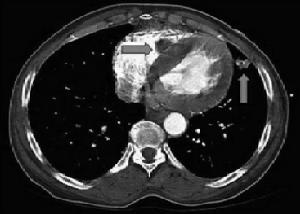

胸部病變與其他系統疾病一樣,周密詳細的病史和體格檢查是診斷呼吸系疾病的基礎,X線胸部檢查對肺部病變具有特殊的的重要作用。由於呼吸系疾病常為全身性疾病的一種表現,還應結合常規化驗及其他特殊檢查結果,進行全面綜合分析,力求作出病因、解剖、病理和功能的診斷。呼吸系統的咳嗽、咳痰、咯血、氣急、哮鳴、胸痛等症狀,雖為一般肺部所共有,但仍各有一定的特點,可能為診斷提供參考。